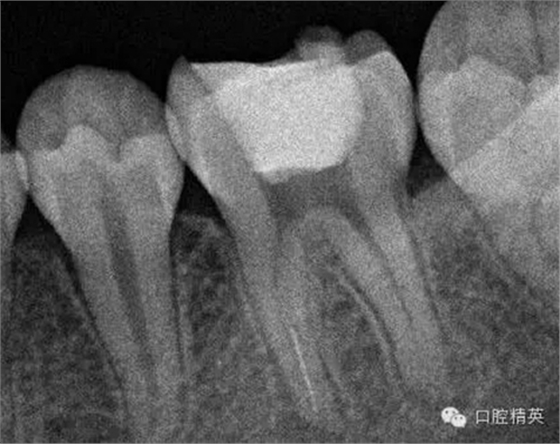

3,術(shù)前左下6近中根管斷針X-P,斷針長度約4MM,根尖慢性炎癥影像。。。

4,去除暫補材料,根管口已暴露